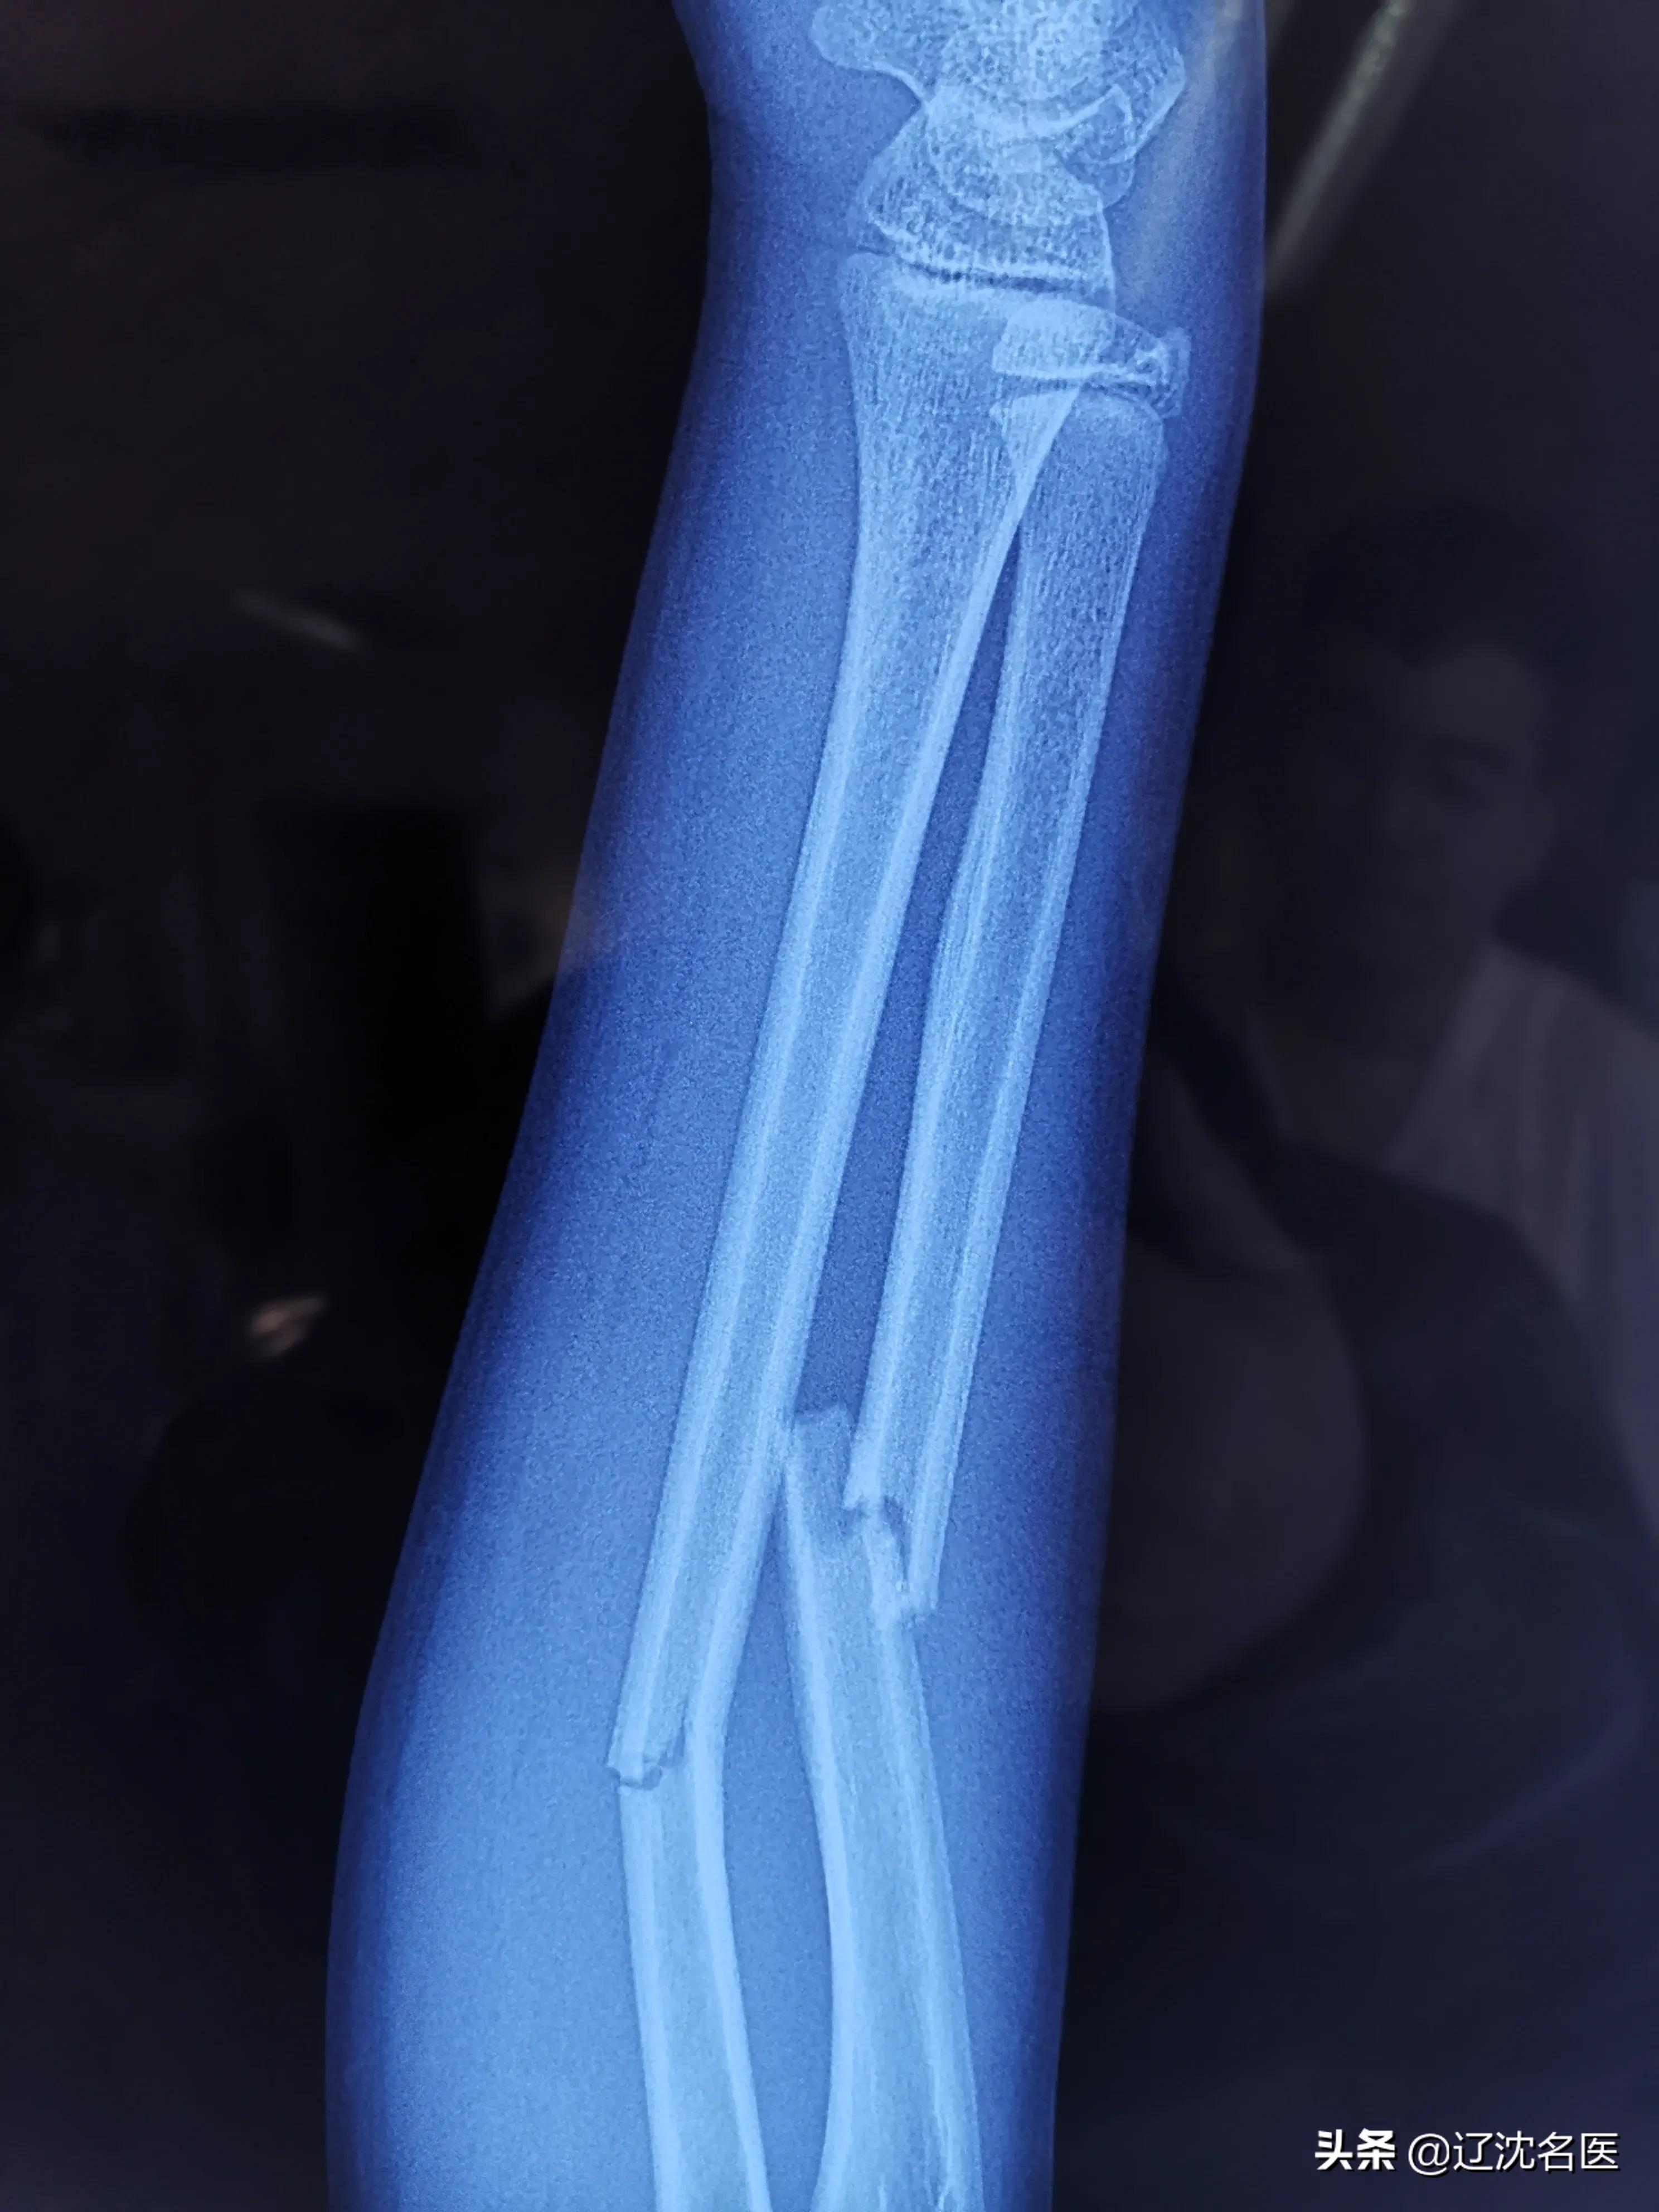

患者是一位12岁的小男孩,因骑自行车摔伤致右前臂肿胀、疼痛、活动受限,在父母焦急的陪伴下来到沈阳医学院附属中心医院急诊就诊,经X线检查诊断为“右尺、桡骨双骨折”。

骨折为不稳定骨折,移位明显,如果采用非手术治疗不能取得满意的复位效果,会影响患儿的上肢功能,必须进行手术治疗。

(术前X线:尺桡骨双骨折,短缩成角移位;腕部骨骺未闭合)